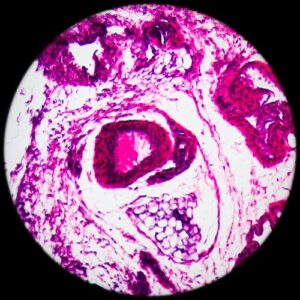

Лейкемия диагностируется на основании подробного анамнеза пациента и медицинского осмотра. После обследования проводится общий анализ крови и мазок периферической крови. В мазке периферической крови клетки крови исследуются под микроскопом. Если в этих тестах обнаруживаются аномальные клетки крови, диагностируется лейкемия. Однако окончательный диагноз ставится путем взятия костного мозга и его исследования в лаборатории патологии, генетики и проточной цитометрии.